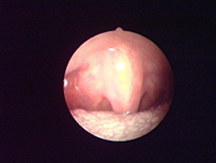

對軟組織切口的比較